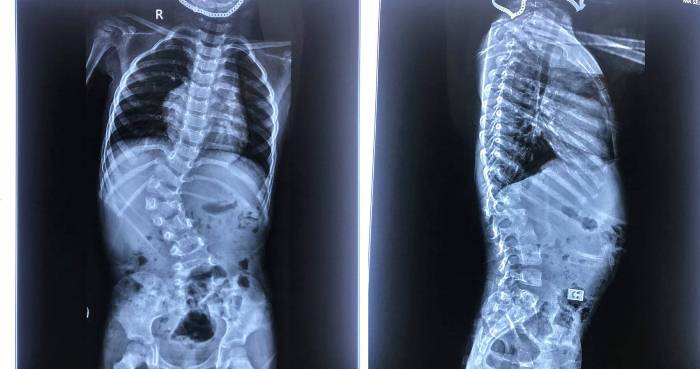

TS.BS Phan Trọng Hậu – Chủ nhiệm Khoa Chấn thương và chỉnh hình cột sống, Bệnh viện TWQĐ 108 cho biết, vẹo cột sống là bệnh lý của cột sống gây ảnh hưởng tới cấu trúc và hình dáng sinh lý của con người. Nếu không phát hiện sớm và điều trị kịp thời, vẹo cột sống sẽ tiến triển ngày càng trầm trọng và gây ảnh hưởng nhiều tới chất lượng cuộc sống.

Người bị vẹo cột sống sẽ gặp nhiều khó khăn trong sinh hoạt hàng ngày, tác động không nhỏ đến chức năng hô hấp và tim mạch. Đặc biệt, khi bị vẹo cột sống, người bệnh còn có tâm lý tự ti khi tham gia các hoạt động tại cộng đồng.

Việc phát hiện gù, vẹo cột sống ở trẻ em sớm và điều trị kịp thời sẽ góp phần ngăn chặn và giảm thiểu những biến chứng gây biến dạng nặng cột sống và ảnh hưởng nghiêm trọng đến sự phát triển của các cơ quan nội tạng khác như phổi, lồng ngực, đồng thời gây ra thiểu sản lồng ngực, phế nang, gây suy hô hấp, đe dọa đến sức khỏe, tính mạng của trẻ.

Nếu nhẹ hơn bệnh có thể gây ảnh hưởng thẩm mỹ, khiến trẻ tự ti, ảnh hưởng đến phát triển tâm sinh lý. Việc phát hiện và điều trị kịp thời sẽ giúp trẻ ngăn chặn gù, vẹo tiến triển nặng hơn, tránh được những ca phẫu thuật không đáng có và thay đổi toàn bộ chất lượng cuộc sống của trẻ, TS Hậu cho biết thêm.